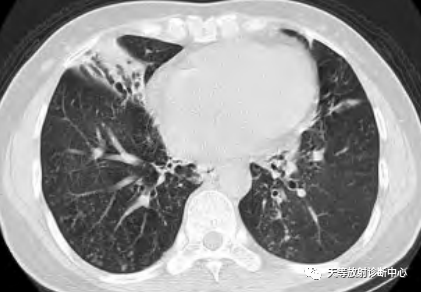

上图注:来源《肺部CT精解》.原著 Kyung Soo Lee.Joungho Han. Man Pyo Chung.Yeon Joo Jeong.主审:许乙凯.王贵生.主译:吴元魁.蔡开灿。